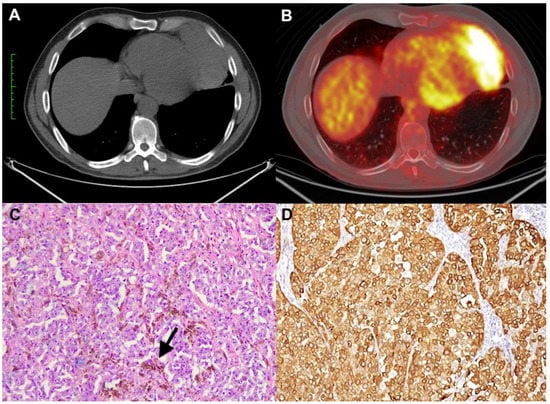

The second patient was a 62-year-old man with a history of skin melanoma of the cervical region which had been surgically resected in 2016. The pathological stage was pT2a, and the tumor harbored the BRAF V600E mutation. One year later a distant relapse to the right foot occurred and was treated with radiotherapy and immunotherapy. After almost five years of controlled disease, a total body CT scan revealed a retrosternal well-defined mediastinal mass of 27 × 30 × 44 mm (Figure 2A), hypermetabolic (SUV = 11.8) at 18-FDG-PET/CT scan. The case was discussed in a multidisciplinary setting; considering the unique localization without metastases in other sites and the radiological features of the mass, a surgical approach was proposed because a primitive neoplasm of the thymus was suspected. A standard robotic-assisted thymectomy was performed. Gross examination showed a brownish nodular mass (Figure 2B). At histology, the tumor was composed of irregularly shaped and eosinophilic neoplastic cells, strongly and diffusely immunoreactive for melanocytic markers (SOX10, Melan A, S100, HMB45). Based on histological and immunohistochemical examination, the diagnosis of intrathymic metastasis of melanoma was made (Figure 2C,D). A large panel of NGS was carried out to identify rare mutations or co-mutations that may have occurred. The tumor showed BRAF mutation (V600E) as the primitive melanoma. No additional mutation has been reported. After surgery, the patient started adjuvant treatment with Nivolumab at a dosage of 480 mg every 4 weeks. Currently, the patient has completed eight cycles of treatment with no reported toxicities. One year after surgery, the patient remains under follow-up and is in good health.

Figure 2. CT scan showing a well-defined retrosternal mediastinal mass (A). Gross specimen showing a nodular mass, which is brownish at the cut surface (B). The tumor was composed of large and atypical cells with abundant eosinophilic cytoplasm (C) (hematoxylin and eosin stain, original magnification ×100). Tumor cells showing nuclear positivity for SOX10 (D) (immunohistochemistry, original magnification ×200)).